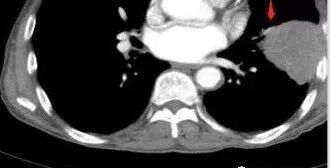

老年男性,外伤入院,“左上肺”实性肿块,边缘光滑,突破壁层胸膜并侵犯肋骨及肋间肌,增强扫描轻度强化,可见明显坏死。

• 胸CT:左肺上叶实性占位,病灶与支气管无关,病灶对斜裂挤压,病灶周围光滑,未见分叶、毛刺;纵隔窗可见病灶内低密度区,病灶对胸壁侵袭,并可见肋骨破坏。

胸CT:左上肺实性大肿块,边缘光滑,突破胸膜侵犯肋骨及肋间肌,纵隔淋巴结肿大,增强呈轻度强化,可见明显片状坏死。